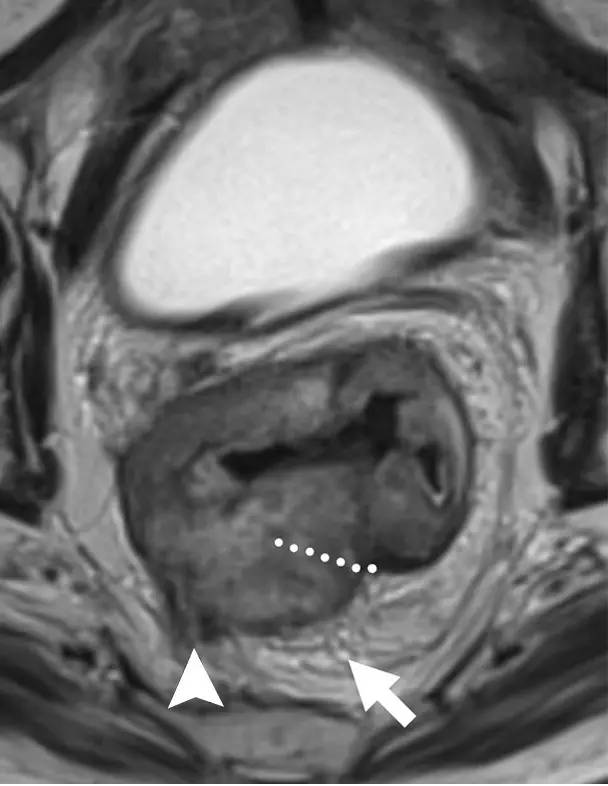

环周切缘 CRM

直肠系膜筋膜是包围直肠周围脂肪和直肠的低信号,代表 TME 切除术中的手术切除平面。在 MR 图像上,是进行 TME 手术患者的潜在 CRM。CRM 阳性是局部复发和预后差的一个重要的独立预后因素。

图 32 轴向 T2 加权图像报告 CRM 的距离。T3c 肿瘤,靠近腹膜的 EMVI(白色箭头)和不规则信号强度淋巴结的 T3c 肿瘤,通过毗邻直肠系膜筋膜的淋巴结包膜(黑色箭头)肿瘤扩展(预测 CRM = 0 mm)。